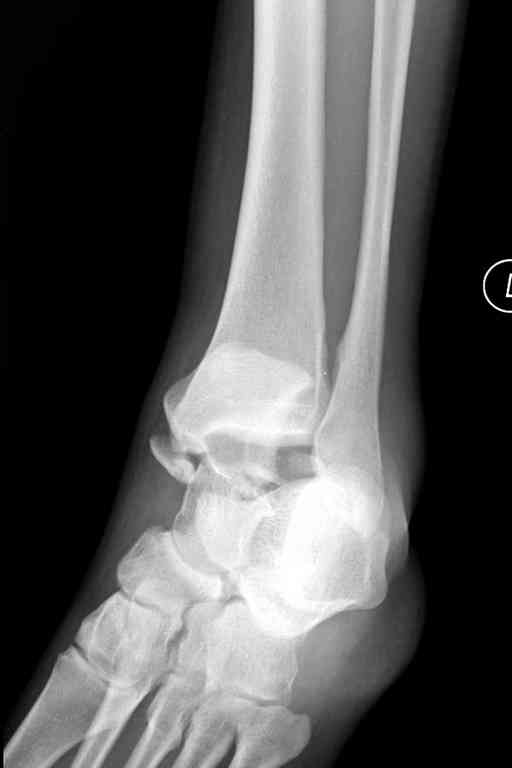

Здесь на фото примеры:

Переломовывих тарана с повреждением медиальной стороны. Через 4 часа после поступления проведена репозиция и фиксация тарана после Irrigation&Debridment. Частичное несращение медиальной лодыжки не беспокоит, вернулся к активному образу жизни. Полная нагрузка разрешена через 11 недель. Финальные снимки через 11 месяцев.